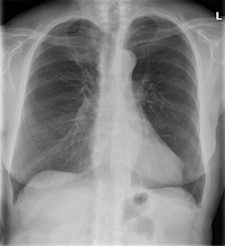

In the quest to diagnose mild-stage chronic obstructive pulmonary disease (COPD), radiologists often use chest radiographs, but Dutch researchers of a new study advise that they shouldn't do so because it results in substantial overdiagnosis.

Chronic obstructive pulmonary disease is usually diagnosed and classified by spirometry. However, in patients with respiratory symptoms, a chest radiograph is generally the first test performed, and, thus, radiologists often mention COPD, frequently as an incidental finding.

The researchers defined COPD using the Global Initiative for Chronic Obstructive Lung Disease (GOLD) classification system. They used a digital flat-panel detector system with a tube potential of 125 kV and determined the mAs value using automated exposure control. Both a posteroanterior (PA) and a lateral chest radiograph were acquired for each patient.

Two senior radiology residents and one board-certified chest radiologist with more than 10 years of experience in thoracic radiology assessed for COPD signs on the radiographs. Observers were blinded for COPD status and did not have access to clinical information. To assess interobserver variability, each of the three observers scored 30 randomly selected patients. All observers scored overall appearance of the chest radiographs specific for COPD.